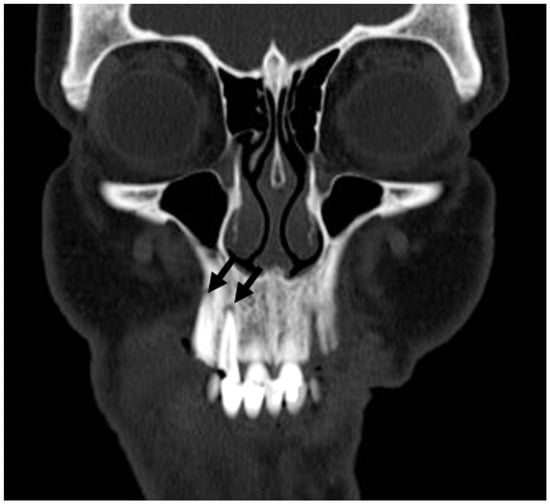

3.5. Anatomical and Imaging Correlations to Odontogenic Infectious Disease

3.5.2. Dental Decay Radiologic Correlations

3.5.4. Periodontal Disease Radiologic Correlations